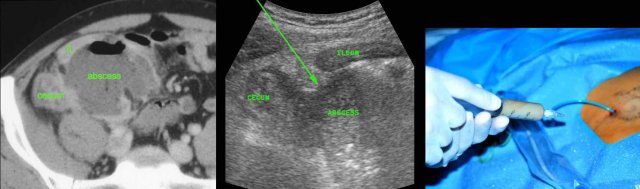

Man of 70 years, with a large abscess in the RLQ.

On CT the appendix could not be identified.

US confirms an inflamed appendix (arrow).

If an appendiceal abscess is demonstrated and there is absent or only mild peritonitis, percutaneous drainage is the treatment of choice.

CT is necessary to confirm the diagnosis, to delineate the extent of the abscess and to determine a safe access route.

Drainage using a combination of US and fluoroscopy has several advantages over CT guided drainage: it is rapid, allows continuous control, any angulation and the use of compression during the procedure.

This patient had a large appendiceal abscess, walled-off by ileum and cecum.

A small window (arrow) allowed US-guided puncture.

Insertion of the drain over a guidewire was done under fluoroscopic control.

In this obese patient, drainage with the US probe using compression, allows the needle to approach the abscess closely.

Note that compression here reduced the distance skin-to-abscess from10 to 3.5 cm.